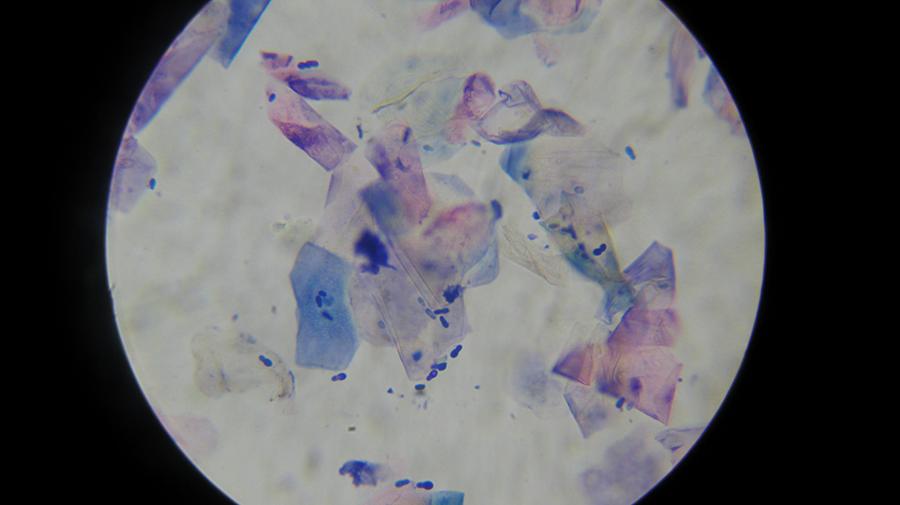

Εργαστηριακές εξετάσεις (αίματος, βιοχημικές, ανοσολογικές, ορμονολογικές, μοριακές τεχνικές)

Εργαστηριακές εξετάσεις

(αίματος, βιοχημικές, ανοσολογικές, ορμονολογικές,

μοριακές τεχνικές)

Το κτηνιατρείο hm vets αναλαμβάνει ψηφιακή ακτινογραφία, έλεγχο δυσπλασίας ισχίου, ορθοπεδική-νευροχειρουργική, χειρουργική μαλακών μορίων, οφθαλμολογία, εσωτερική παθολογία και εργαστηριακές εξετάσεις (αίματος, βιοχημικές, ανοσολογικές, ορμονολογικες, μοριακές και ιστοπαθολογικές).

Το κτηνιατρείο hm vets αναλαμβάνει ψηφιακή ακτινογραφία, έλεγχο δυσπλασίας ισχίου, ορθοπεδική-νευροχειρουργική, χειρουργική μαλακών μορίων, οφθαλμολογία, εσωτερική παθολογία και εργαστηριακές εξετάσεις (αίματος, βιοχημικές, ανοσολογικές, ορμονολογικες, μοριακές και ιστοπαθολογικές).